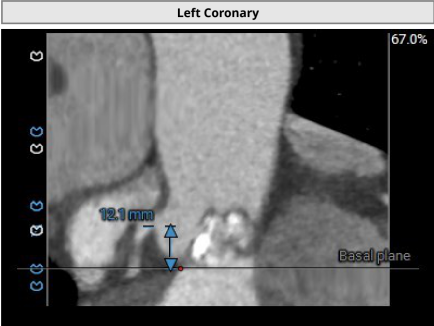

2. 冠脉开口高度尚可,左右冠瓣叶冗长,切线位左右冠瓣叶长度>>冠脉开口到瓣叶根部附着缘距离;冠脉未见明显钙化斑块;

• 左右冠瓣叶冗长,切线位左右冠瓣叶长度>>冠脉开口到瓣叶根部附着缘距离,结合瓦氏窦、STJ、钙化分布特点综合预估冠脉堵塞风险偏高,术中球扩时密切关注冠脉血流灌注,备冠脉保护方案;

冠脉阻挡风险及钙化评估